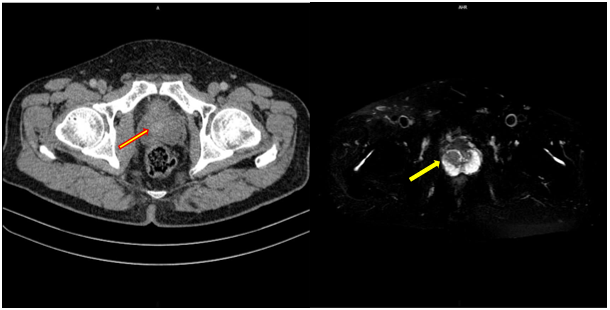

Điều trị ung thư tuyến tiền liệt bằng phương pháp cấy hạt phóng xạ (Radioactive Seed Implantation Therapy) I-125

Điều trị ung thư tuyến tiền liệt bằng phương pháp cấy hạt phóng xạ (Radioactive Seed Implantation Therapy) I-125 GS.TS....